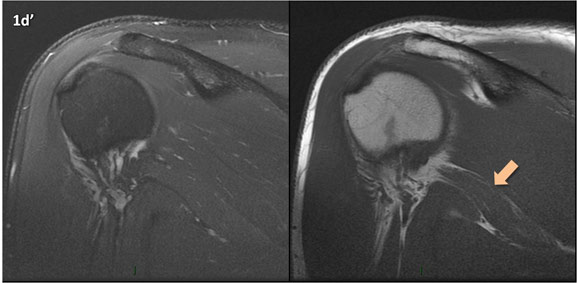

Figura 1 (a-g): Imagens consecutivas de RM no plano coronal nas ponderações DP com supressão de gordura (DP SG) à esquerda e T1 à direita. Clique na seta para passar as imagens.

Figura 1 (a-g)': Imagens consecutivas de RM no plano coronal nas ponderações DP com supressão de gordura (DP SG) à esquerda e T1 à direita mostrando . Clique na seta para passar as imagens.

Figuras 1b’ a 1g’ mostrando atrofia da porção superior do músculo redondo menor (seta salmão), com lipossubstituição mais evidente das mais fibras laterais (seta amarela). As fibras mais inferiores e mediais têm atrofia menos evidente.

Repare que estas alterações não são evidentes nas imagens com supressão de gordura.